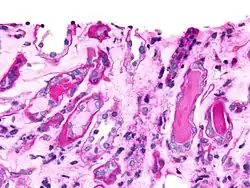

Micrograph showing casts in a kidney biopsy using PAS stain: Hyaline casts are PAS-positive (dark pink/red, right of image). Myelomatous casts are PAS-negative (pale pink, left of image)